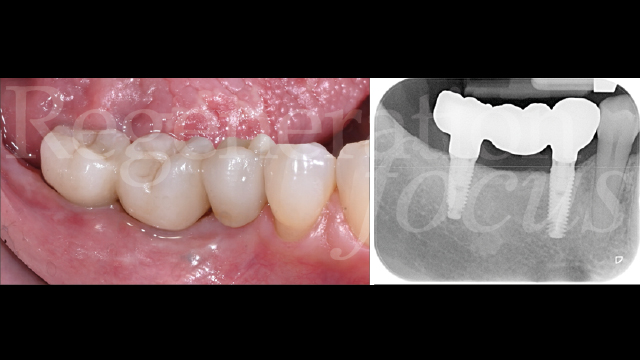

Il periodo di osteointegrazione è trascorso senza complicanze (Fig. 13). A quattro mesi, l’impronta digitale con scanner intraorale ha registrato la morfologia dei tessuti molli maturati (Fig. 14). Le corone monolitiche in zirconia stratificata sono state progettate e realizzate (Odt. Antonio Corradini) con emergenza graduale per supportare i tessuti molli, sfruttando la connessione diretta delle corone protesiche senza l’utilizzo di monconi o cemento, eliminando micro-gap e micro-movimenti in grado di compromettere la stabilità del sigillo biologico (Fig. 15).

Il follow-up clinico e radiografico a 12 mesi ha documentato eccellente stabilità del risultato ottenuto. L’analisi radiografica non ha evidenziato rimodellamento osseo marginale né segni di radiolucenza peri-implantare o alterazioni della trabecolatura ossea (Fig. 16). I parametri clinici peri-implantari hanno mostrato profondità di sondaggio inferiori a 4 mm e assenza completa di sanguinamento al sondaggio. L’analisi del fenotipo tissutale ha documentato incremento significativo dello spessore mucoso e l’analisi del microbioma ha rivelato composizione batterica compatibile con la salute peri-implantare e il mantenimento dell’eubiosi (Figg. 17,18).